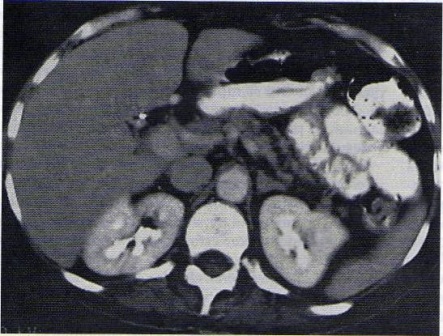

8.1.4. TAC

Tiene buena sensibilidad para el diagnostico de las formas severas y moderadas. Puede mostrar dilataciones, calcificaciones en conductos grandes y pequeños, zonas de atrofia y seudoquistes. Permite ver el estado del parénquima y de los vasos y es útil para el diagnostico diferencial con carcinoma pancreático.

El mejor indicador del estado del páncreas es la TC helicoidal con protocolo para páncreas, la que no sólo es muy apropiada para delinear el contorno pancreático, sino que con frecuencia muestra las calcificaciones en el sistema ductal, cuando están presentes.

Un conducto pancreático normal mide 3 a 4 mm de diámetro en la cabeza y se va afinando hasta 2 a 3 mm en el cuerpo distal y la cola.

Cuando existen estrecheces ductales con prevalencia en la cabeza del páncreas pero que se localizan en todo el conducto, este aspecto de "cadena de lagos" puede ser de gran ayuda para orientar el tratamiento.

Tomografía computarizada que muestra la dilatación irregular del conducto pancreático principal en un paciente con pancreatitis crónica